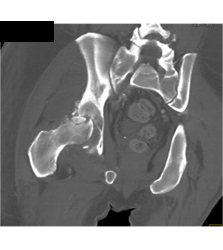

Calcaneal Fracture